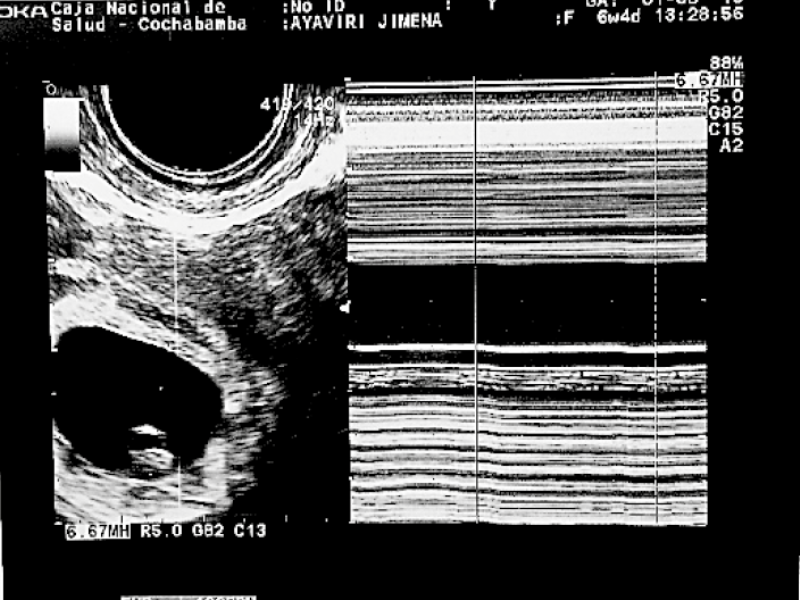

Transvaginal ultrasound revealed uterus in AVF of normal shape and contours, enlarged dimensions at the expense of orthotopic gestational sac with single live 7 mm LCC embryo with cardiac activity ( Figure 1), corresponding to six weeks of gestation, a 31x19 mm ovoid adnexal formation in right adnexa; Douglas with scant free fluid.